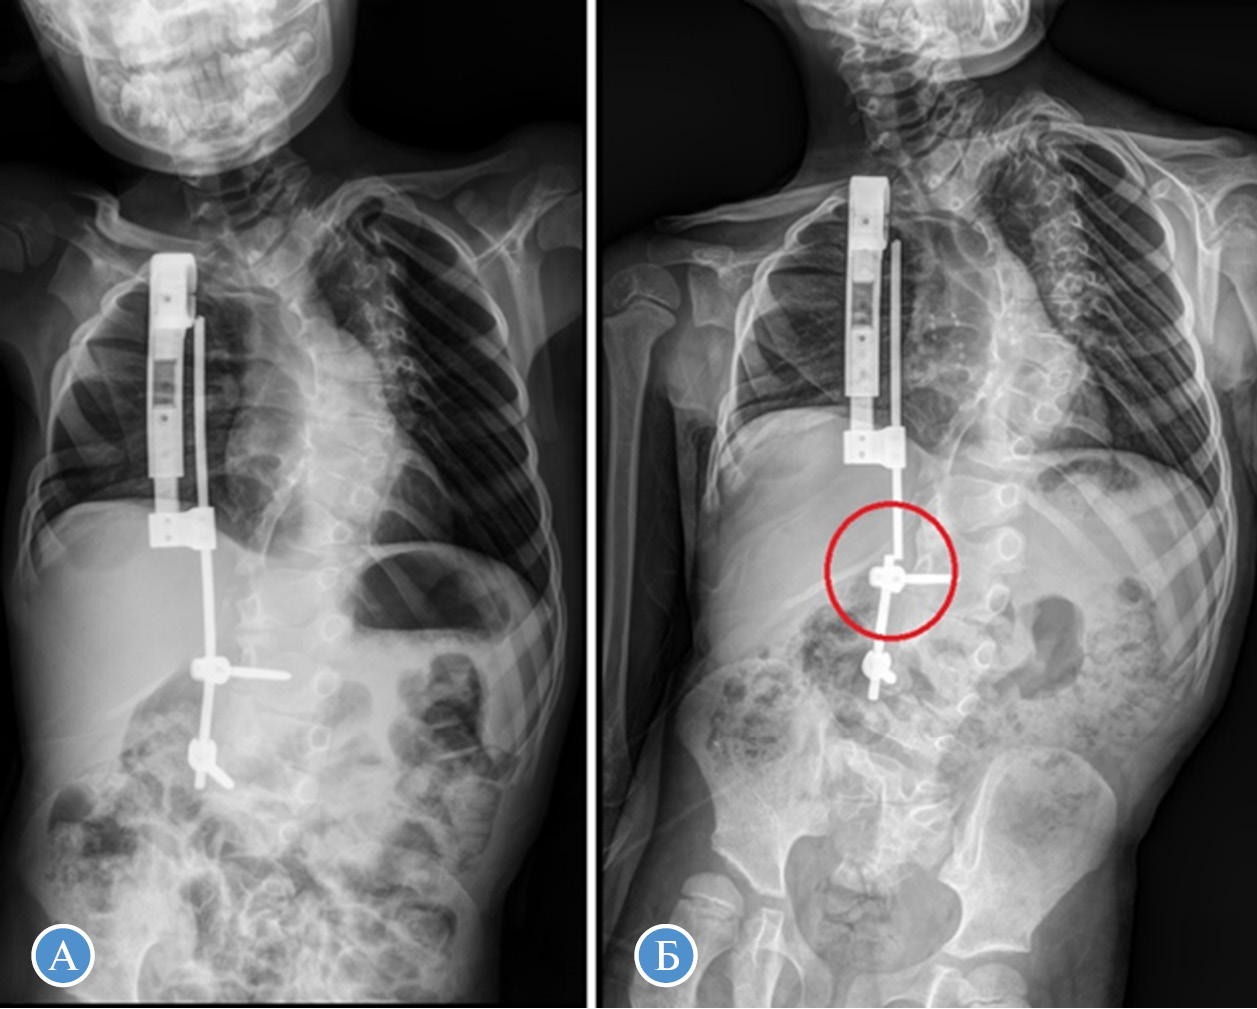

Анализ осложнений хирургического лечения выявил, что у пациентов первой группы в 3 случаях была отмечена дестабилизация металлоконструкции при ростовом скачке и активном наборе детьми массы тела (рис. 6). У пациентов второй группы данный характер осложнений не отмечался.

Рис. 6. Пациент Ф., 6 лет. Диагноз «врожденный сколиоз». А — прослеживается реберно-позвоночный дистрактор, положение правильное, корректное; Б — через 2,5 мес. после выписки, на снимке обозначена область перелома стержня металлоконструкции

У одного пациента первой группы и у двух пациентов второй группы отмечались явления транзиторного неврологического дефицита, проявляющиеся снижением силы верхних конечностей на стороне установки реберно-реберного дистрактора в первой группе и на стороне выполнения клиновидной остеотомии во второй группе, а также развитием синдрома Горнера. Развитие осложнений отмечалось в раннем послеоперационном периоде в случае локализации одностороннего бокового нарушения сегментации позвонков на уровне Th2–Th5, на фоне консервативного лечения отмечался регресс неврологической симптоматики к 14-м сут послеоперационного периода у всех пациентов.